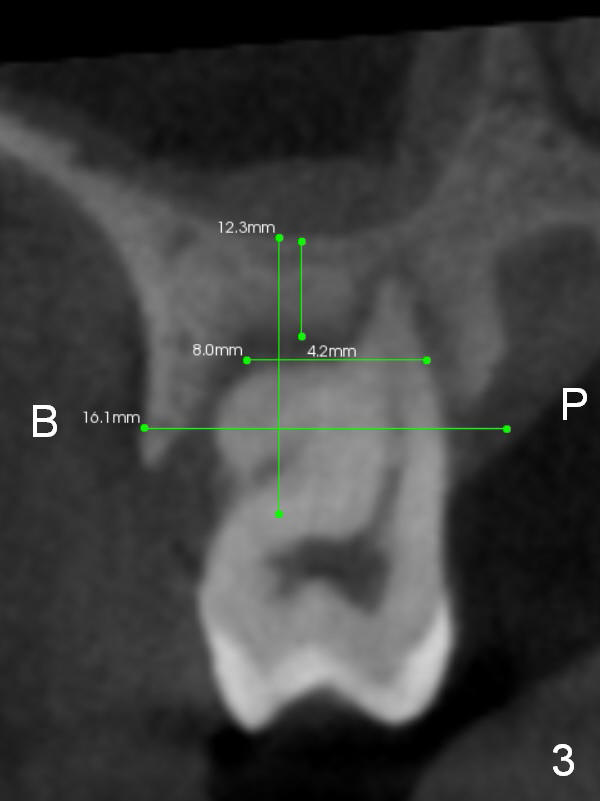

The socket is wider buccopalatally (Fig.2 (3-D disto-occlusal view),3 (coronal section)) than mesiodistally (Fig.1,4 (sagittal section),5 (axial section)). Unless more bone loss has occurred in the last year, a 6x10 mm UF implant is to be placed in the middle of the socket (Fig.6, (soaked with 2% Xylocaine/1:50,000 Epinephrine gauze)) with bone graft to be placed in the buccal and palatal gaps (red circles). Bone density in the middle of the socket is 550-700 Hounsfield units. Use RT2 or 2 mm pilot drill to start osteotomy ~ 3 mm. The largest osteotome is RT4, or largest reamer 4 mm, followed by 4.5x17 mm tap at 14 mm, until 6x17 mm one. Make sure that the sinus floor is penetrated.